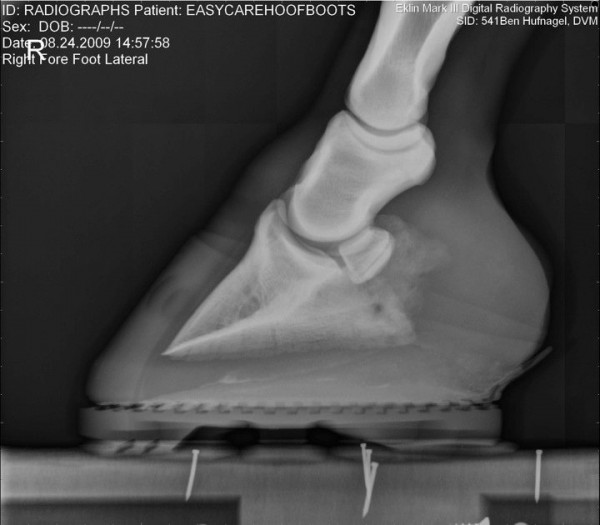

Společnost EasyCare si dělá vlastní průzkumy-výzkumy… zde jsou zajímavé fotografie jak to vypadá když je kopýtko v botě, zůstává ve svém přirozeném tvaru, kopytní mechanismus je neomezený a kůň ho má možnost plně přirozeně využívat 🙂